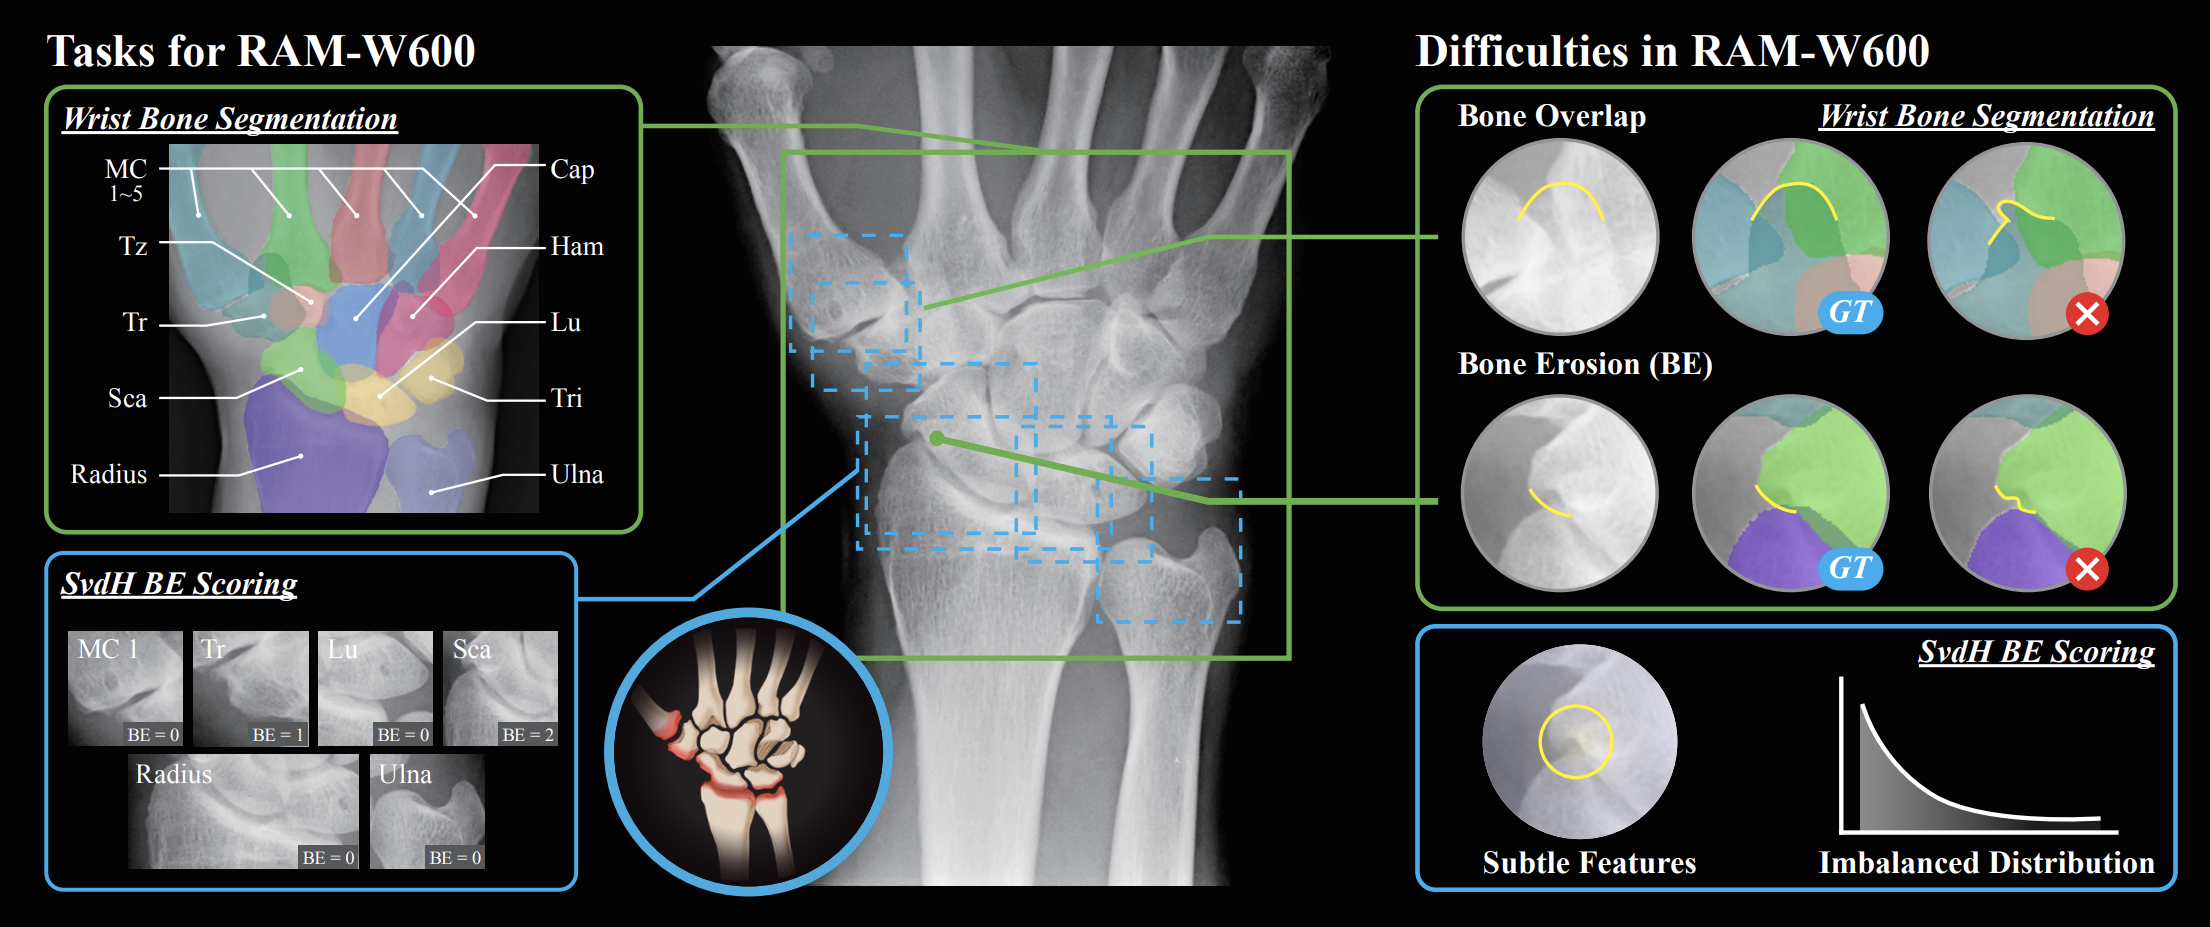

Rheumatoid arthritis (RA) is a common autoimmune disease that has been the focus of research in computer-aided diagnosis (CAD) and disease monitoring. In clinical settings, conventional radiography (CR) is widely used for the screening and evaluation of RA due to its low cost and accessibility. The wrist is a critical region for the diagnosis of RA. However, CAD research in this area remains limited, primarily due to the challenges in acquiring high-quality instance-level annotations. (i) The wrist comprises numerous small bones with narrow joint spaces, complex structures, and frequent overlaps, requiring detailed anatomical knowledge for accurate annotation. (ii) Disease progression in RA often leads to osteophyte, bone erosion (BE), and even bony ankylosis, which alter bone morphology and increase annotation difficulty, necessitating expertise in rheumatology. This work presents a multi-task dataset for wrist bone in CR, including two tasks: (i) wrist bone instance segmentation and (ii) Sharp/van der Heijde (SvdH) BE scoring, which is the first public resource for wrist bone instance segmentation. This dataset comprises 1048 wrist conventional radiographs of 388 patients from six medical centers, with pixel-level instance segmentation annotations for 618 images and SvdH BE scores for 800 images. This dataset can potentially support a wide range of research tasks related to RA, including joint space narrowing (JSN) progression quantification, BE detection, bone deformity evaluation, and osteophyte detection. It may also be applied to other wrist-related tasks, such as carpal bone fracture localization. We hope this dataset will significantly lower the barrier to research on wrist RA and accelerate progress in CAD research within the RA-related domain.